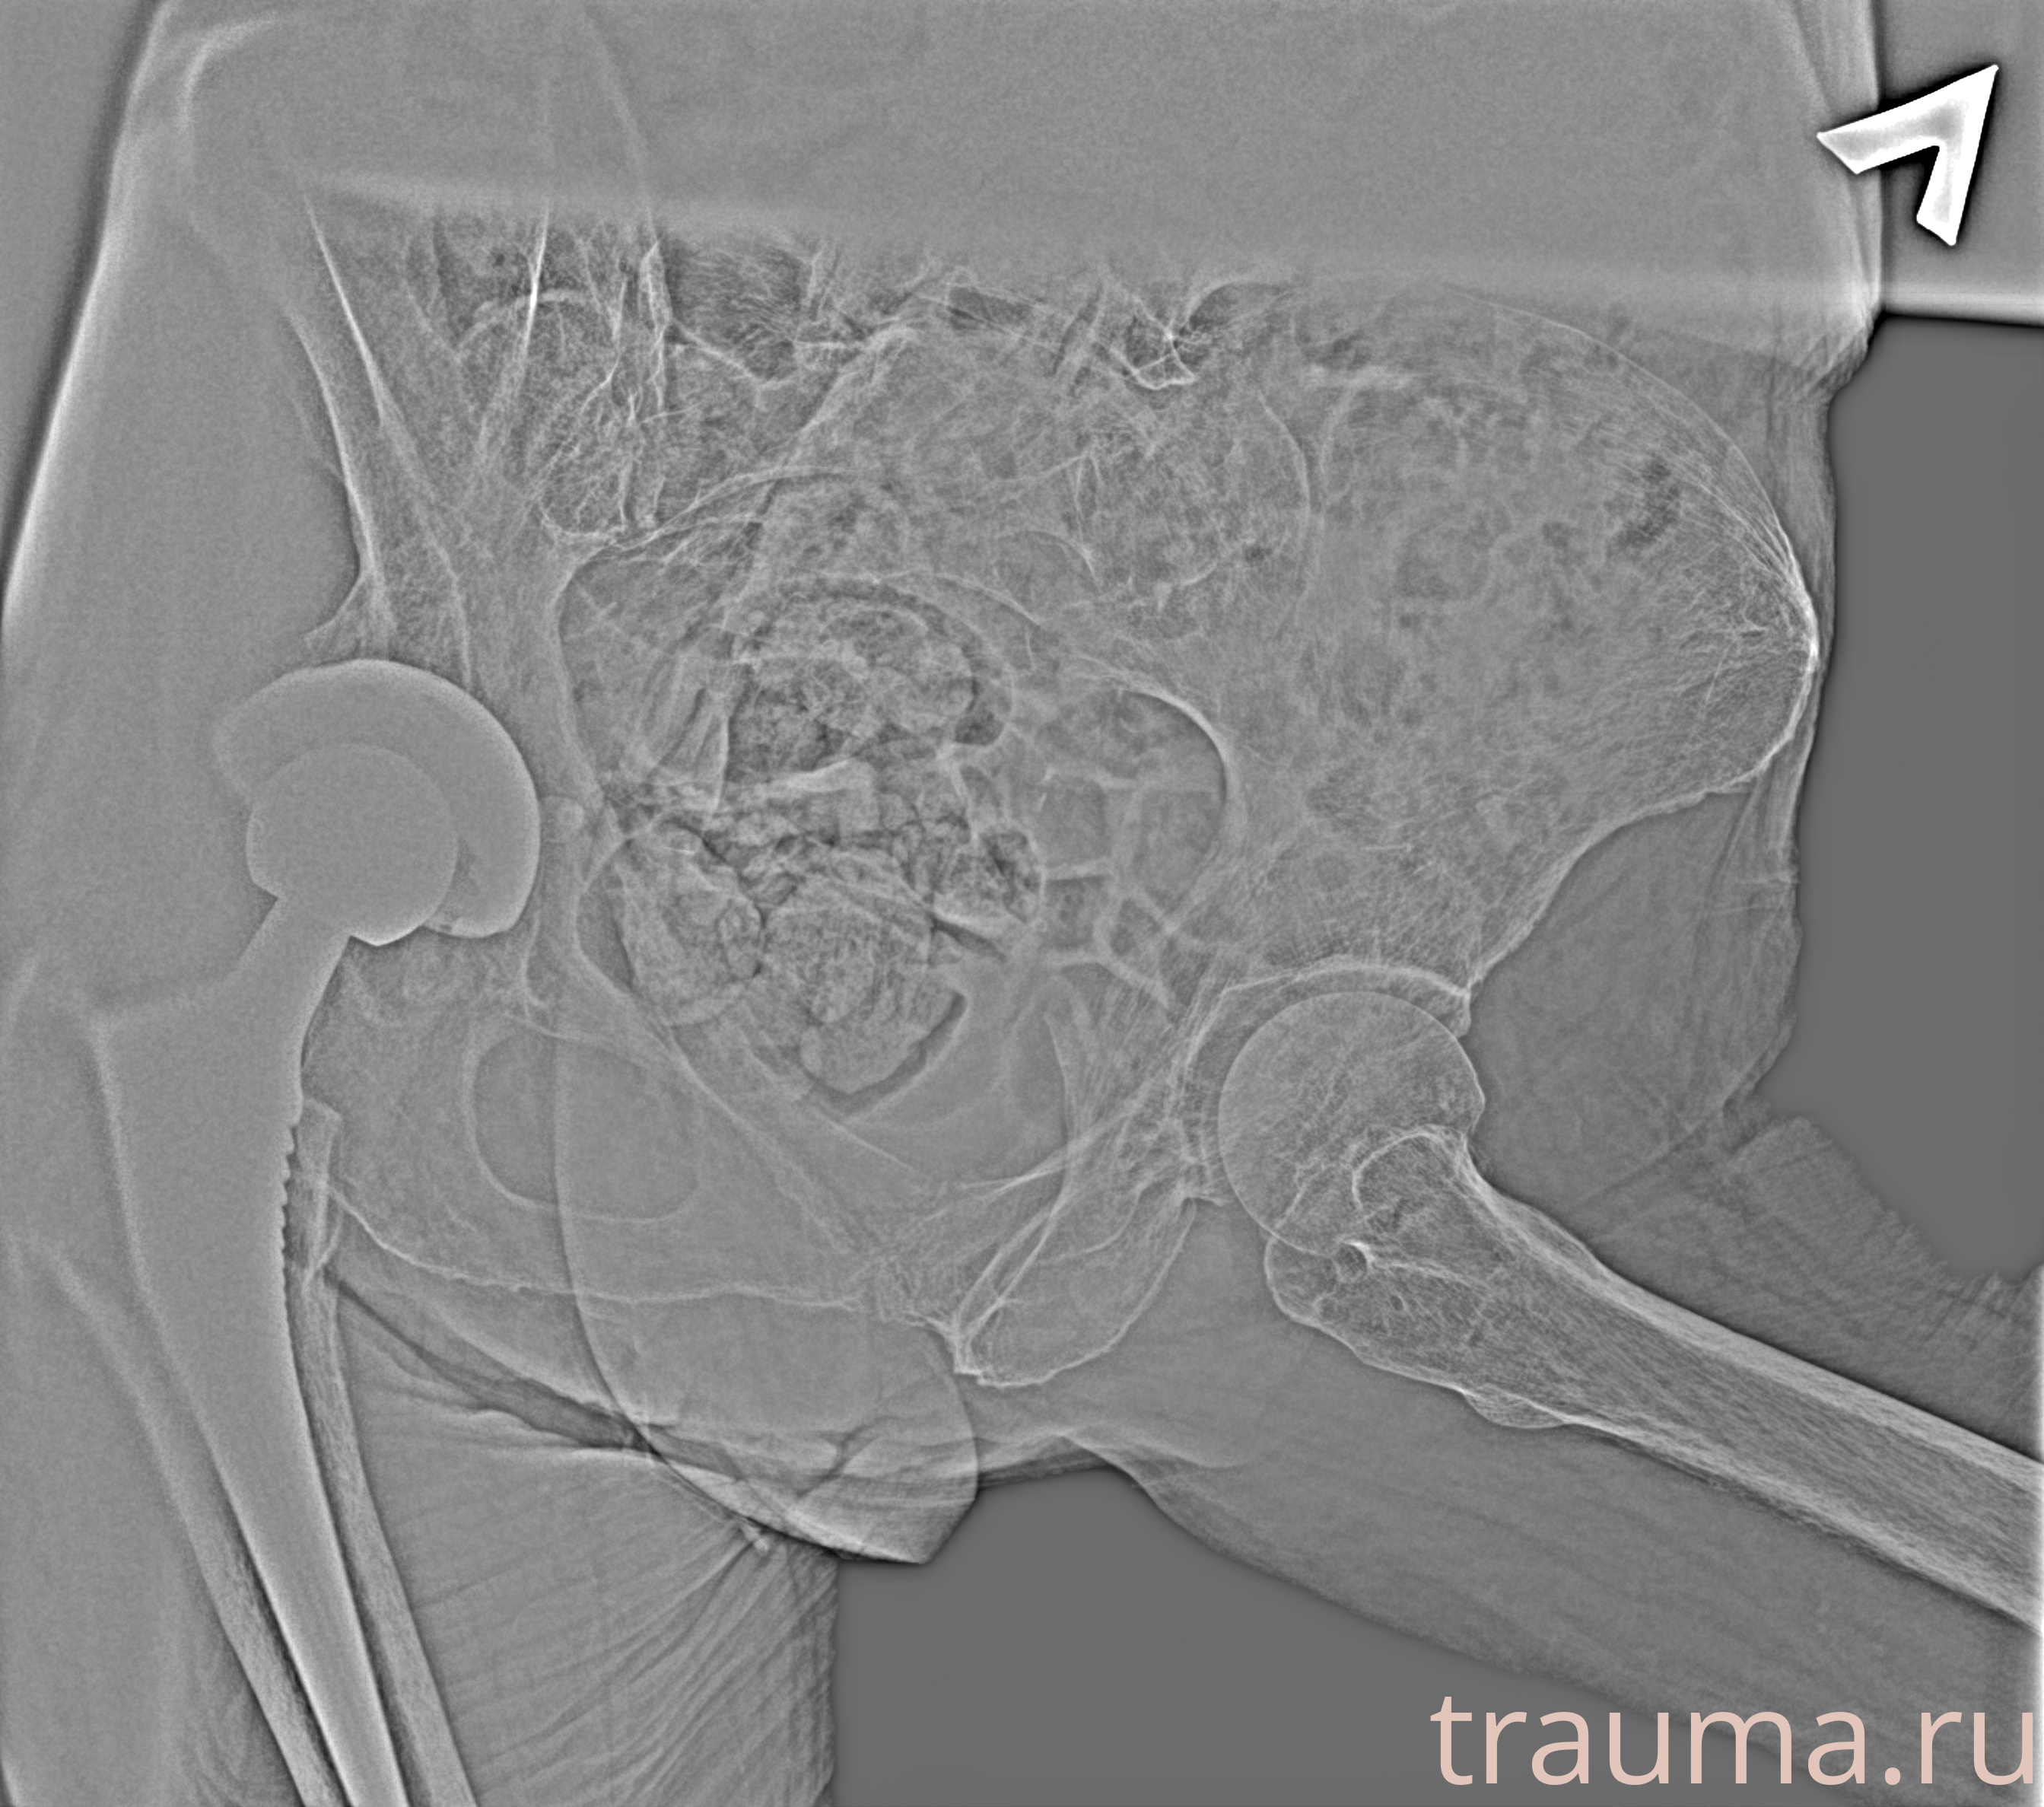

Рентген на дому: по вашему адресу приезжает врач-рентгенолог, травматолог-ортопед с мобильным рентгеновским аппаратом, проводит диагностику травмы или заболевания, делает необходимые рентгенограммы, дает рекомендации по дальнейшему лечению. Получить качественные снимки в домашних условиях возможно благодаря уникальной методике, разработанной МосРентген Центром для института  Склифосовского